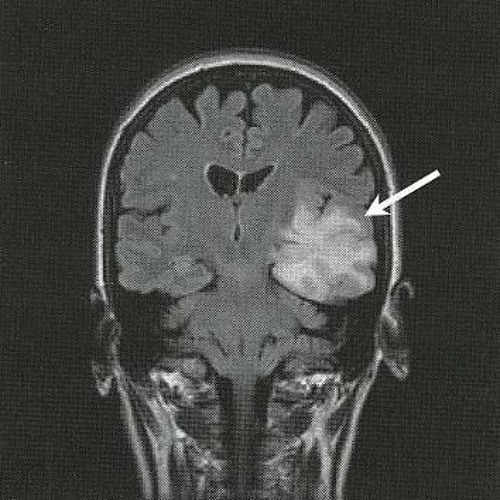

Что значит неоперабельная опухоль

Что значит неоперабельная опухоль 109 фотографий